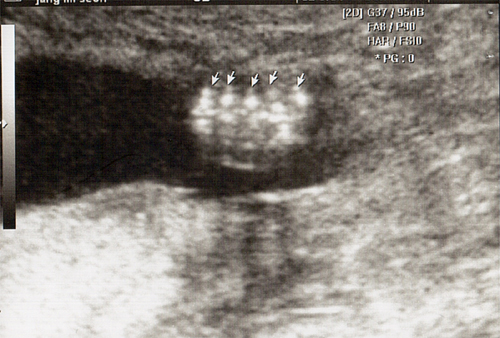

강아 ^^ 21주 강이의 정밀 초음파를 봤어 일반 초음파 보다는 더 정밀하게 나오더라구 엄청 커버린 강이가 한눈에 보이지 않을정도로 이제는 초음파 기계가 작아 보이더라..

암튼 건강하고 아무 이상없이 잘 자라주고있는 강이를 보면 아빠를 힘이나고 더욱 열심히 해야 겠다는 생각이 든단다..